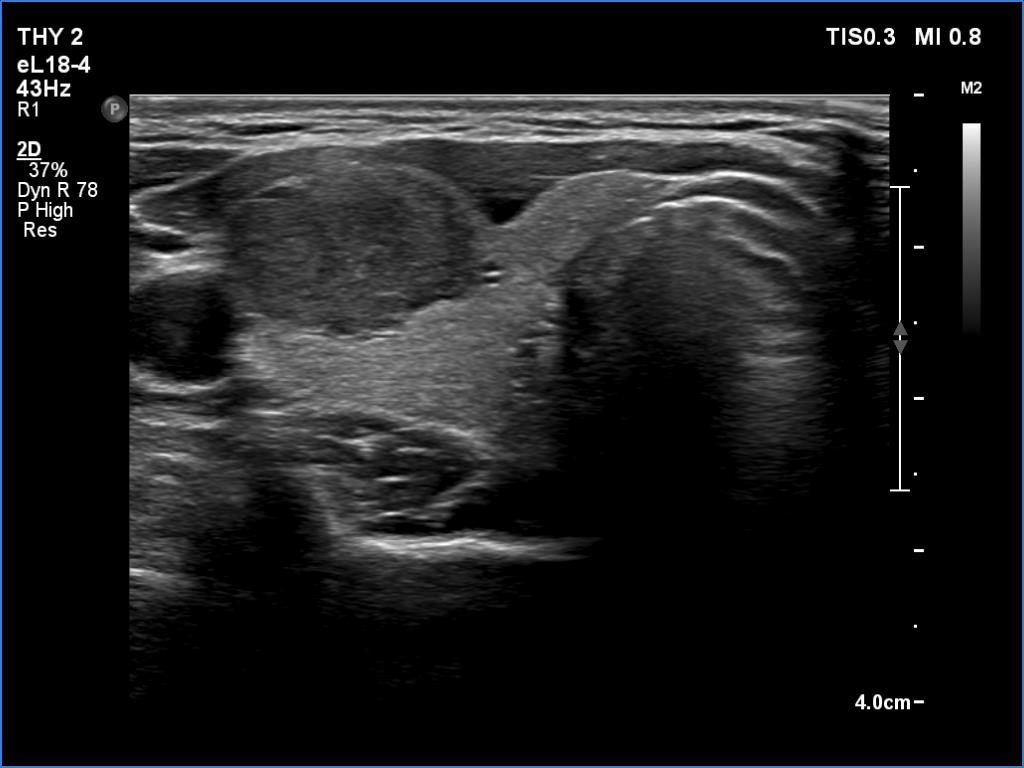

Ultrasonography. The thyroid was echonormal and presented two discrete lesions in the right lobe. The larger, upper one showed irregular margins, abutting and bulging contours and had back wall figures. The intranodular vascularization was significantly increased. The smaller lesion had microcalcifications and presented taller-than-wide shape.

Comment. It is worth thoroughly analyzing the intranodular echogenic figures. These are partly linear and most of them are related to tiny ventral cystic areas.